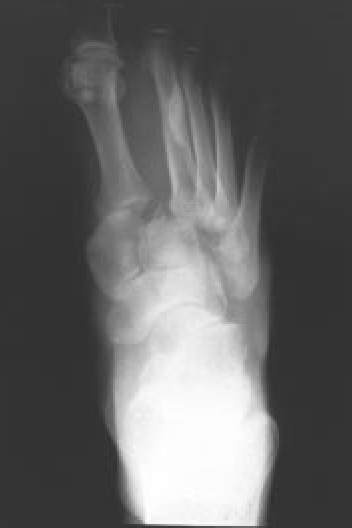

Fig. 5A.: Fractura-luxación de la articulación de Lisfranc